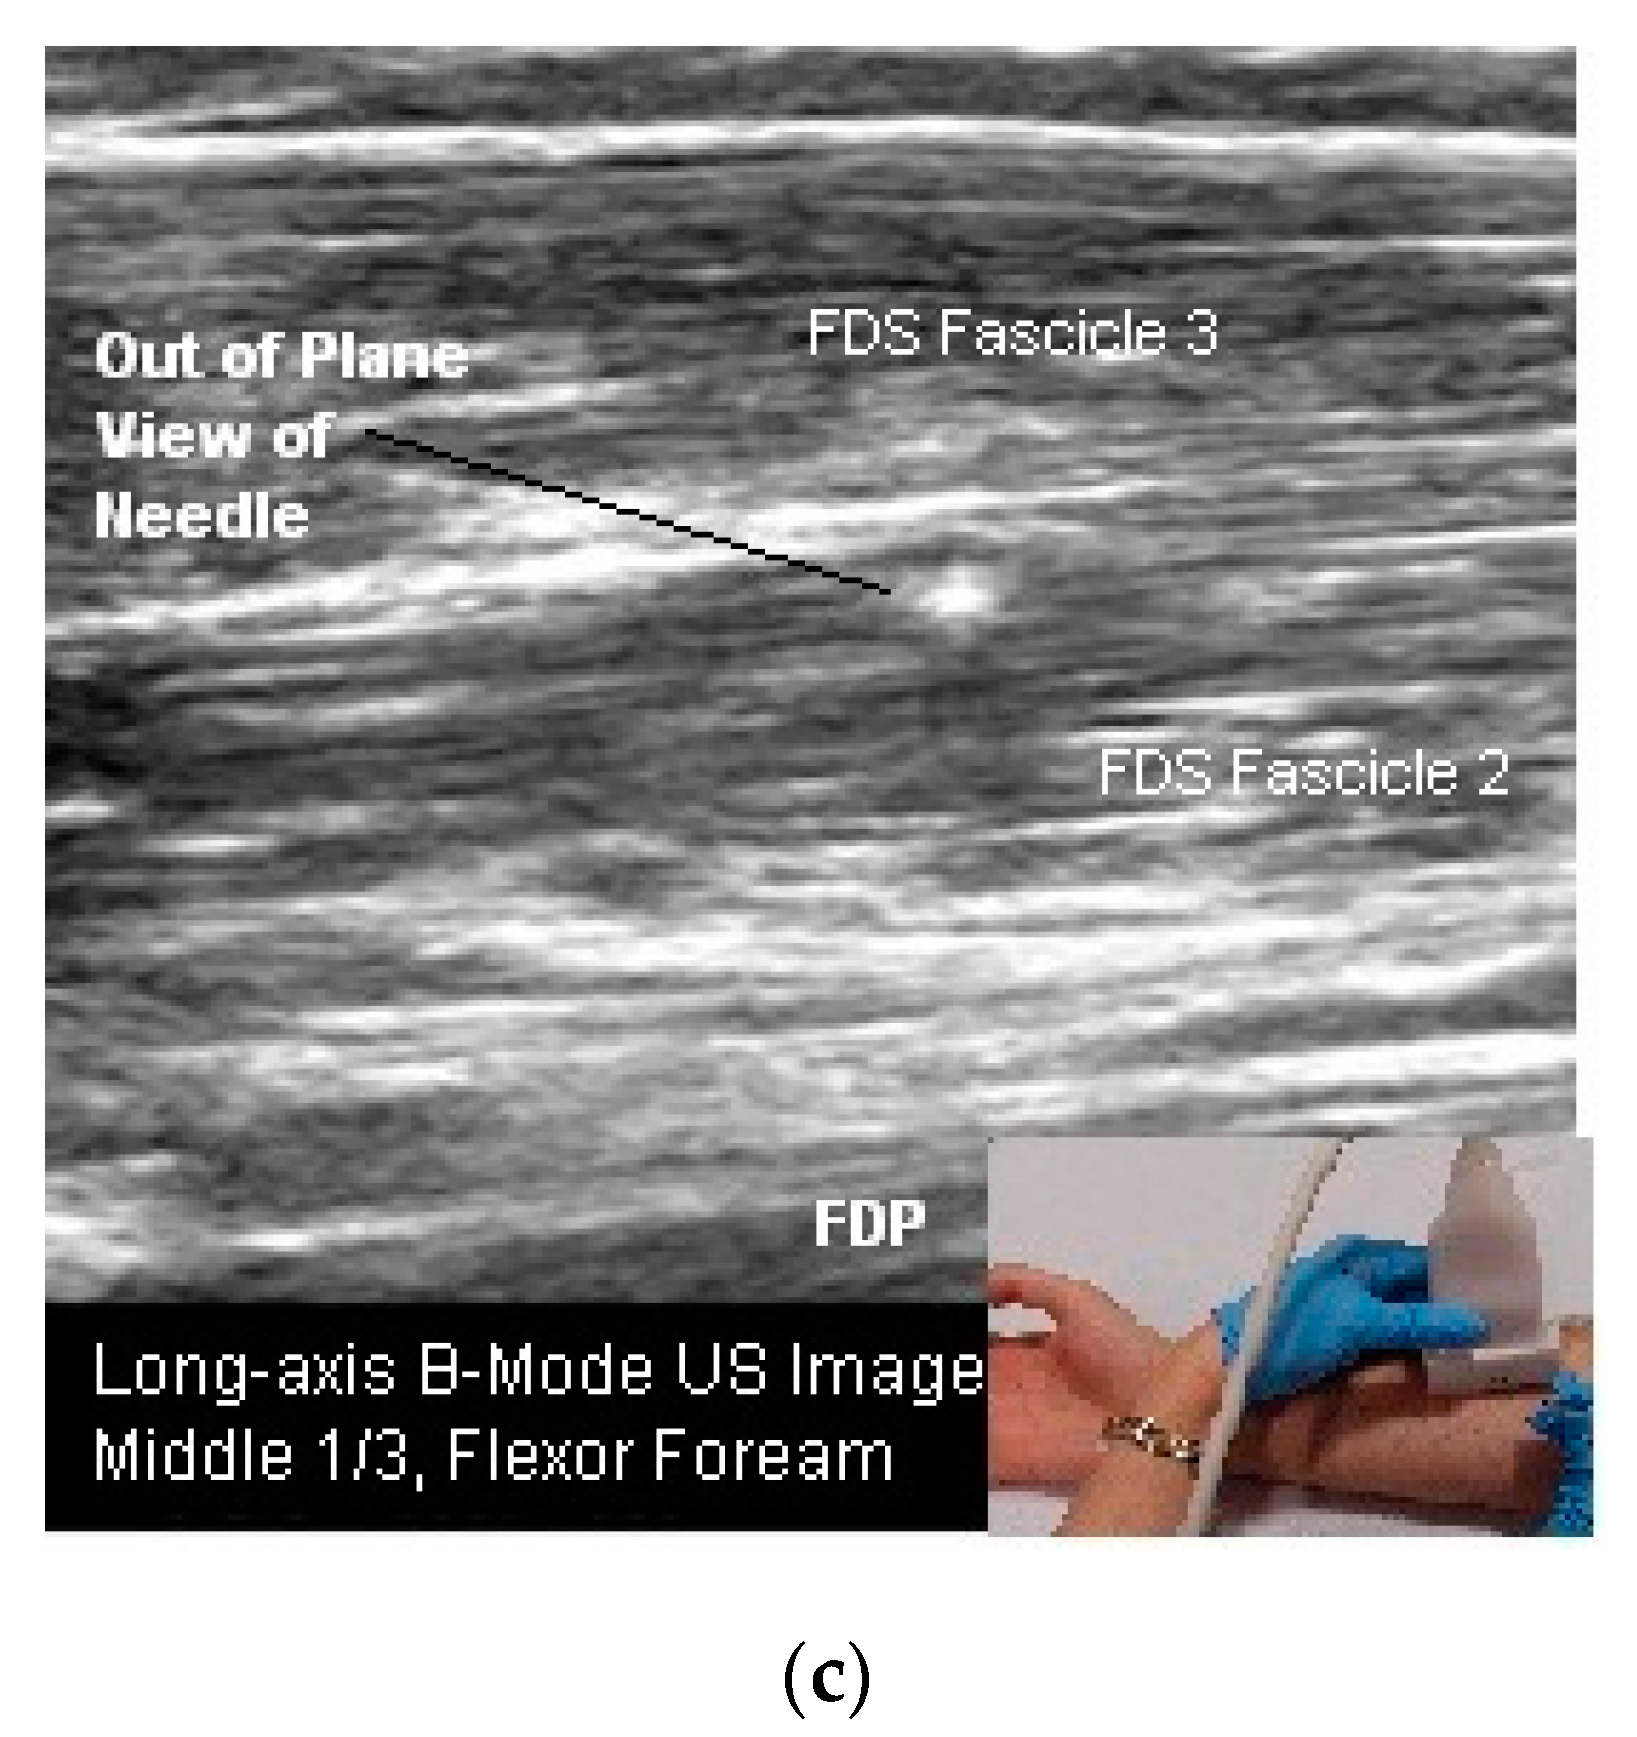

- In Plane Technique (IPT). When using an IPT the needle is inserted along the length of the transducer (Figure 6b and Figure 7a). With the IPT, the entire needle and its tip is visualized, an advantage over the OPT. However, this technique can be challenging to perform because the sonographer must keep the needle within the narrow US beam. Another challenge is that optimal needle visualization requires that the needle be inserted and maintained in an orientation perpendicular to the US beam Figure 8a. When inserted at a steep or oblique angle, visualization of the needle may be lost due to needle anisotropy [24,50,54] (Figure 8b).

- To keep the needle perpendicular to the US beam requires needle insertion to be at a flat angle relative to the transducer (Figure 8a). For superficial structures, such as the sternocleidomastoid muscle, this is easily accomplished. When targeting deeper muscles/structures, the needle must be inserted at some distance from the transducer to maintain an angle that minimizes anisotropy. This often requires a larger gauge, longer needle.